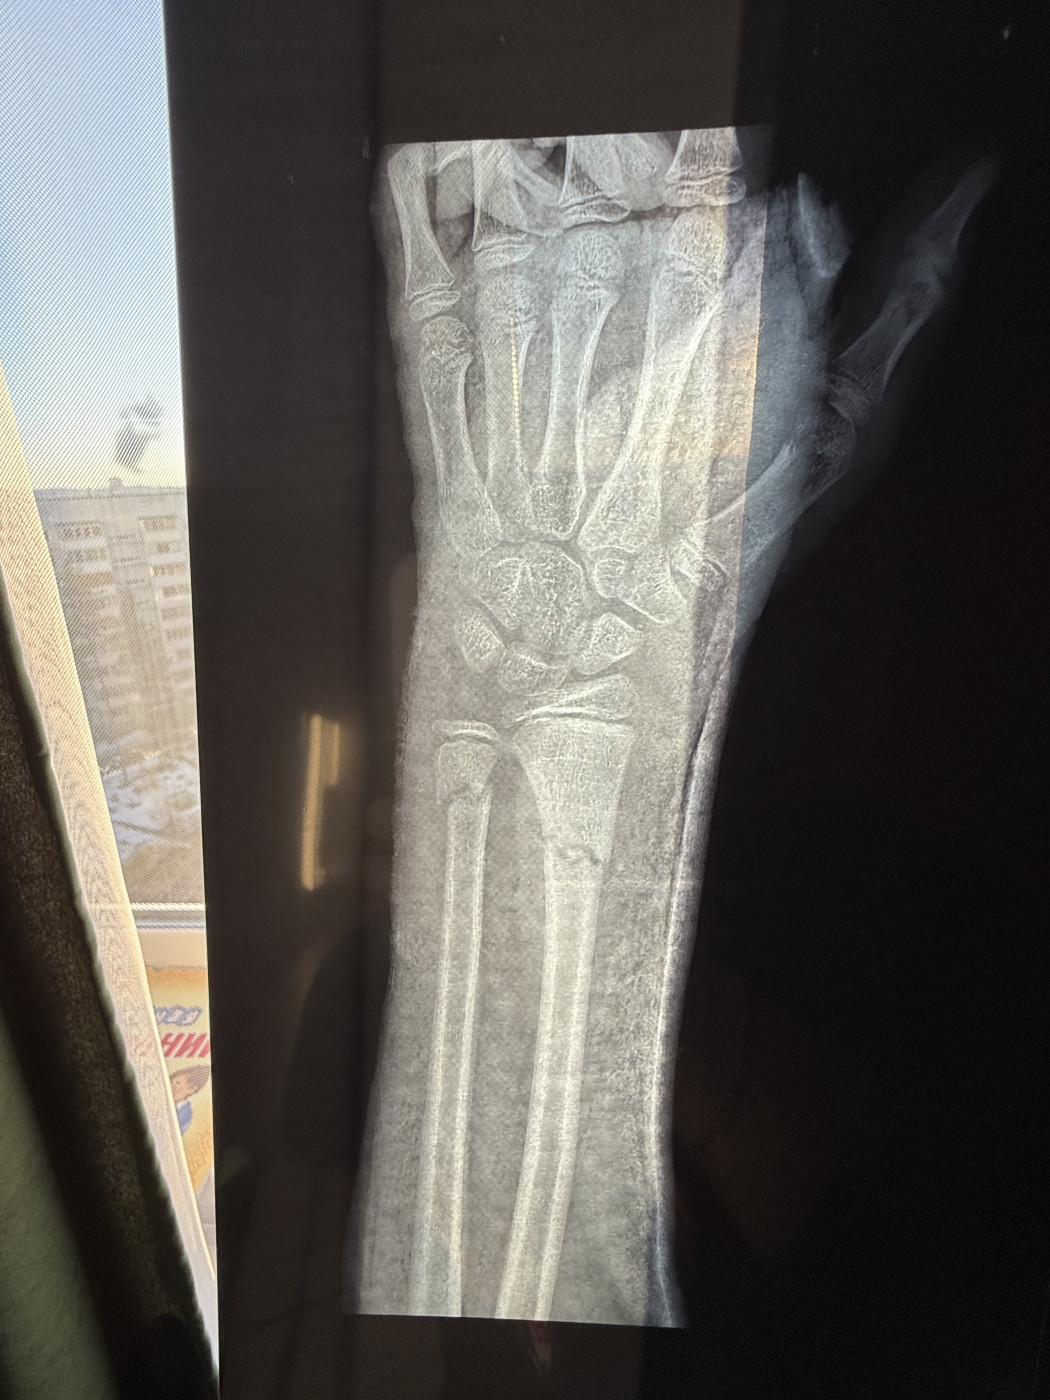

Травма руки   1 ответ

Здравствуйте! Скажите пожалуйста унас травма руки там стоят пластины рука сохнет и не двигается но нас не хотят ставить на инвалидность и щитают что ана ещё будет работать